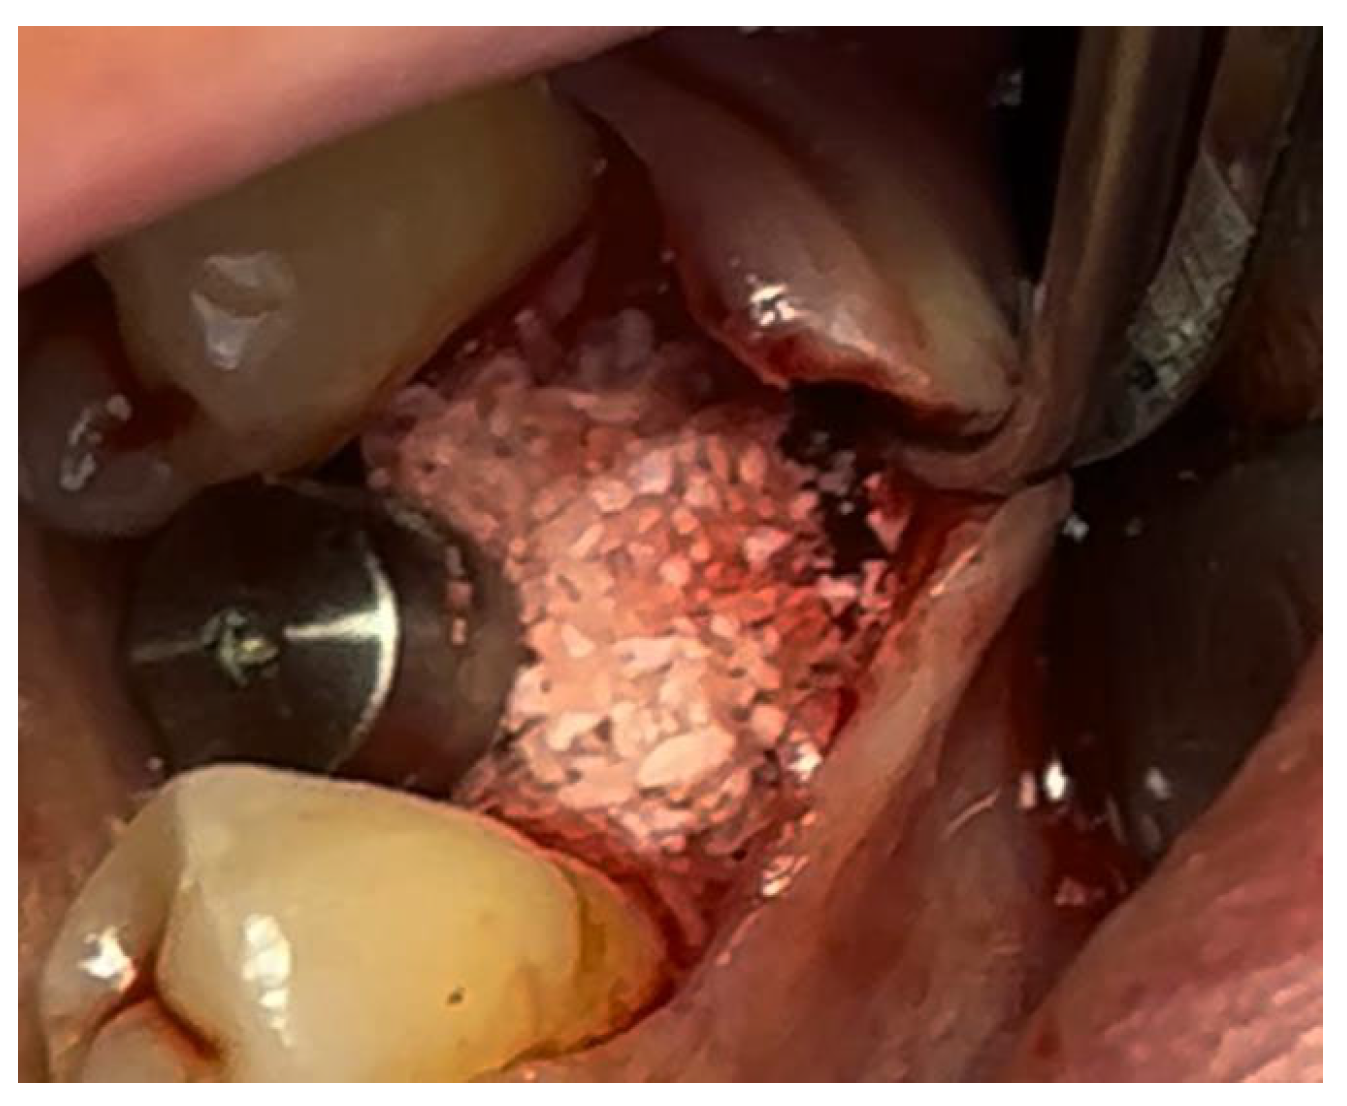

In a 49-year-old patient with ischemic heart disease, Glubran II was used as a stabilizing material for natural bone graft granules at a site rehabilitated with implant-prosthetic treatment, with the aim of achieving volumetric enhancement of the buccal bone. Following specific guidelines for surgical treatment of ischemic heart disease (4), implant therapy was carried out (Figure 8). Natural bone graft material (Bio-Oss®—Geistlich, Baden-Baden, Germany) was applied and stabilized with Glubran II. The application was made using an endodontic needle, depositing single droplets of the glue to cover the entire graft material before placing the prepared flap on top (Figure 9). This technique achieved stable graft fixation at the recipient site, demonstrating the efficacy of Glubran II for internal use (Figure 10).

Figure 9. Stabilization of bone regeneration material with Glubran II.

Materials 18 02642 g009